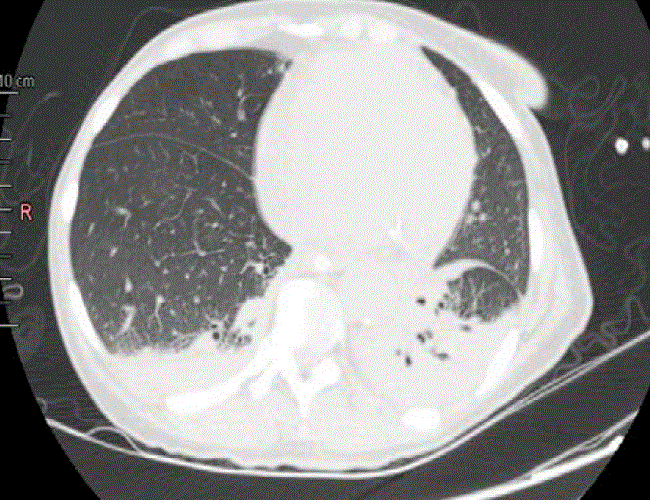

En la tomografía computadorizada (TC) de cerebro, se observó hidrocefalia con ventriculomegalia e hipodensidades periventriculares (figura 1) y en la de tórax de alta resolución, un patrón en vidrio esmerilado con atelectasia del lóbulo inferior pulmonar izquierdo (figura 2).